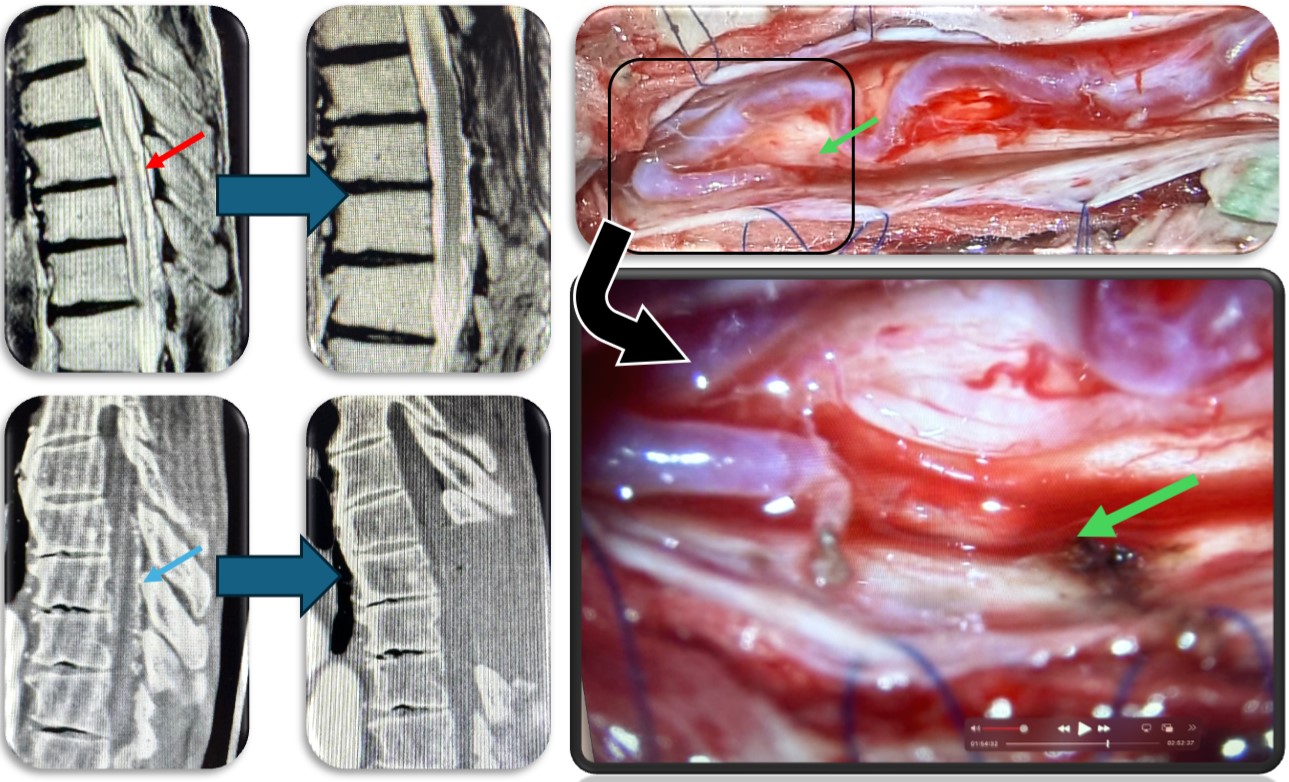

(代表例①)

硬膜動静脈瘻の症例です。脊髄血管奇形の中では最も多い疾患です。脊髄の静脈に動脈血流が直接流入する事により脊髄浮腫をきたし(赤矢印)、様々な神経症状が出ます。最近では血管内から治療することもありますが根治率は20%程度と非常に低く、基本的には高い確率で根治できる外科的治療を施します。当院では基本的には外科的治療を選択しますが、高齢者や外科的治療が困難な症例では血管内治療を検討することもあります。手術では動脈から静脈に直接流入する部位(緑矢印)を焼灼離断します。術直後に脊髄浮腫は改善し、造影CT検査で描出の認めた異常血管影(青矢印)は術後に消失しました。